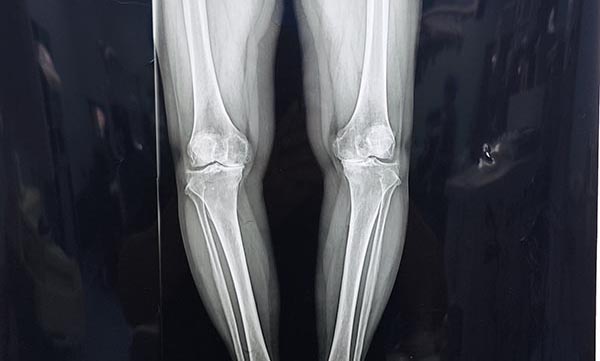

今年59岁的孙女士长期被左侧膝关节骨性关节病困扰,近一年来病情持续加重,行走百余米便出现剧烈疼痛,上下楼梯需扶手借力,日常生活深受影响。她于11月3日慕名前往海城市正骨医院老年骨伤病科住院就诊。入院后,付伟团队为孙女士完善了膝关节X线、CT及磁共振成像等全套检查,影像学结果显示其左侧膝关节软骨严重磨损、内侧间隙明显变窄,伴骨赘形成及轻度内翻畸形,符合膝关节置换手术指征。考虑到孙女士希望术后快速康复、恢复高质量生活的需求,医院随即组织多学科专家会诊,最终敲定“机器人辅助下左侧人工全膝关节置换”的手术方案。